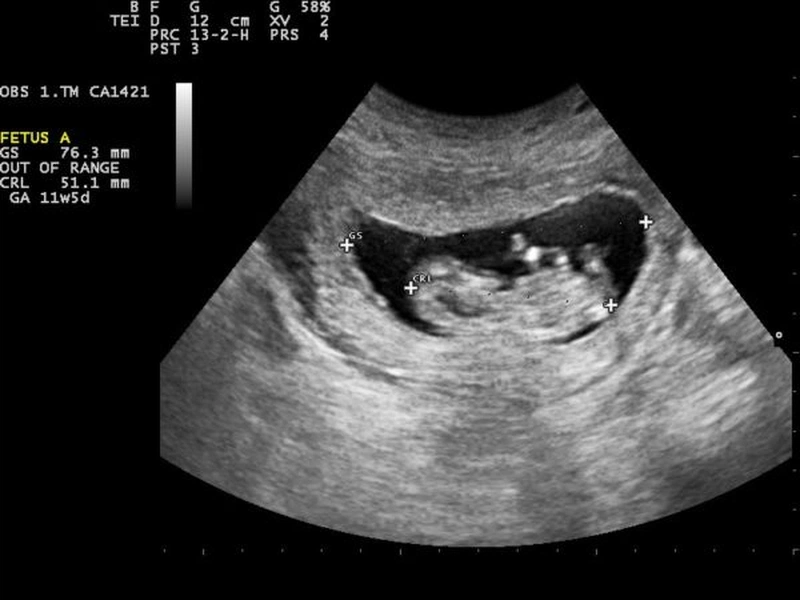

Bác sĩ có thể đo chiều dài của phôi để đánh giá sự phát triển của thai nhi và xác định các yếu tố nguy cơ. Khi chiều dài của phôi vượt quá 5mm mà không có nhịp tim, có thể là dấu hiệu của tình trạng hư thai. Trong trường hợp túi thai lớn hơn 10mm mà không có túi noãn hoặc vượt quá 20mm mà không có túi noãn hoặc phôi, tiên lượng sức khỏe thai nhi là rất kém.